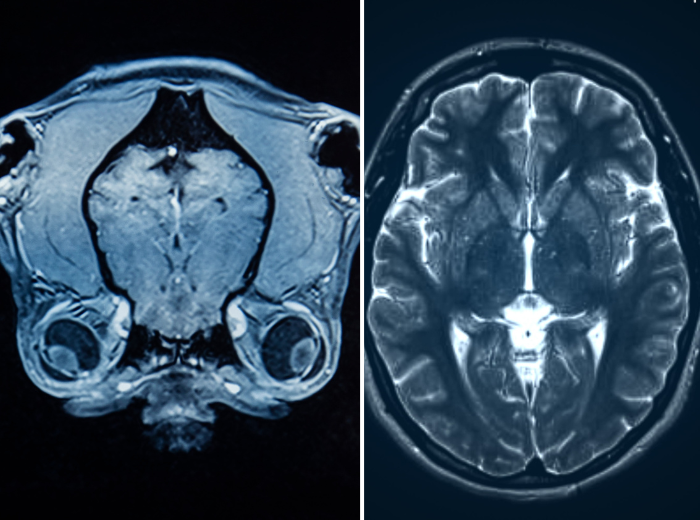

To really understand what makes dogs dogs, it helps to compare their brains to ours:

- Dogs’ brains are much smaller relative to body size than human brains, roughly a 1:125 brain-to-body mass ratio, compared with about 1:40 in humans.

- Their prefrontal cortex (involved in higher thinking) is much smaller, in dogs it occupies only about 10 % of the brain, vs nearly one-third in humans.

- Dogs aren’t little humans. Their cognition is organized differently, with instincts, social processing, and sensory prioritization often taking precedence over abstract reasoning.

- Humans have highly folded brains with vast surface area, giving us advanced capacities for planning, language, self-reflection, and abstract thought.

- Our brain structure supports cognitive skills that go well beyond what even the smartest dog can achieve.

The differences don’t mean one species is “better”, just adapted for different roles. Dogs have been shaped by thousands of years of close co-evolution with humans, leading to brain structures finely tuned for social interaction, empathy, and partnership with people.